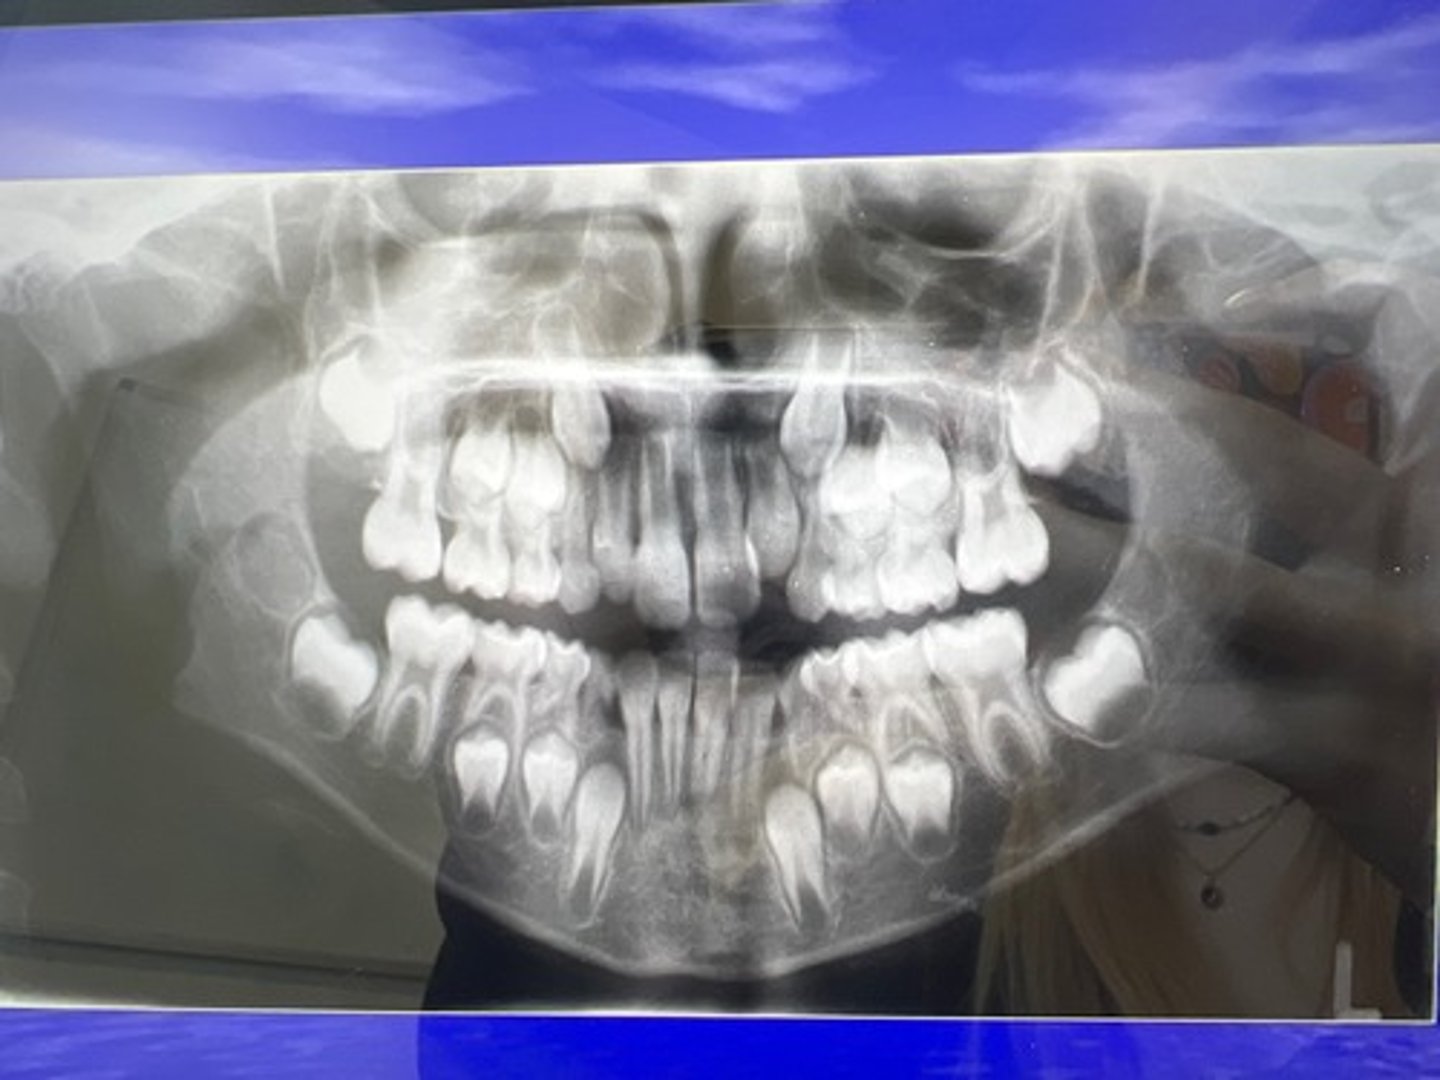

Example of a child OPG x-ray: